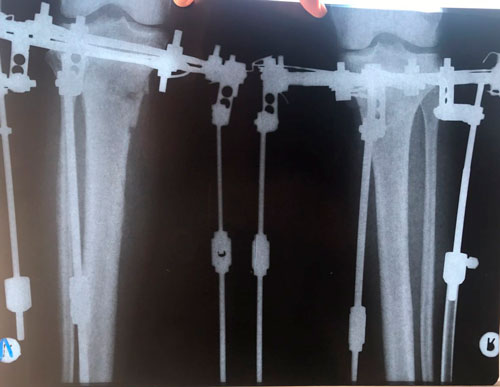

Дата операции 21.03.2018г.

Дата снятия аппаратов 06.07.2018г.

Срок лечения 105 дней.